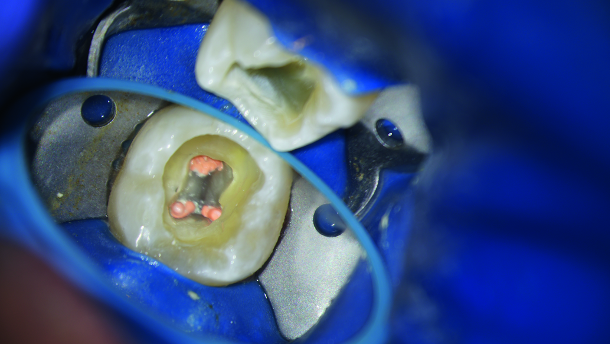

To create a suitable glide path, both mesiobuccal and mesiolingual canals were handfiled to a size 15 file. All pulpal tissue was removed after opening the pulp chamber and canal clearance was checked thoroughly. For the actual preparation, the use of a universal EDM file in ISO size 25 totally sufficed (Fig. 5). With the flexible file we were able to instrument the mesial canals to a working length of 22 mm. Keeping its pre-bent shape, the instrument permitted to work without any stress and when the apex was gauged in the distal canal, a size 30 hand file seemed to fit in quite comfortably. Consequently, a 40/0.04 HyFlex EDM finishing file was used to enlarge the apical aspect of the two distal canals. It is important to point out that thorough irrigation was performed with sodium hypochlorite between every file. At the end of the procedure the canals were irrigated with NaOCI, EDTA and CHX under acoustic streaming. The canals were then dried via microsuction followed by the insertion of the corresponding paper points. In the end, the canals were obturated with the help of the traditional warm vertical compaction technique (Fig. 6).The pulpal floor was sealed with a layer of glass ionomer, sponge pellet (to act as a spacer) and a dualcured temporary filling material consisting of zinc oxide and zinc sulphate over the top. A post- op radiograph was obtained (Fig. 7) and after the successful endodontic treatment the patient was subsequently referred to his general dentist for the definitive restoration of the tooth.